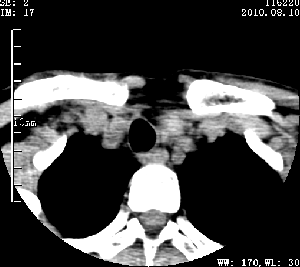

标题: CT28317:病人近几天无意间发现颈部肿块。 [打印本页]

标题: CT28317:病人近几天无意间发现颈部肿块。

甲状腺左叶局限性结节性甲状腺肿可能。建议增强扫描。

病变边界清楚,周围间隙清晰,甲状腺左叶(甲状旁腺?)肿大,右叶甲状腺腺瘤。

病变边界清楚,周围间隙清晰,左叶甲状腺肿大,右叶甲状腺小腺瘤。